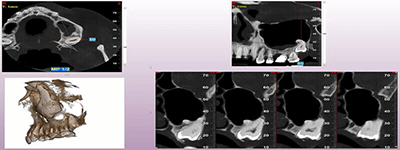

Proactive Dental Management thru our 3D Imaging Manipulation Software

With Oral Maxillofacial CT Scans, your dentist enhances his ability to proactively manage your health concern thru accurate diagnosis & better treatment planning. Moreover, the patient benefits from a painless,low radiation dose CT Scan procedure.